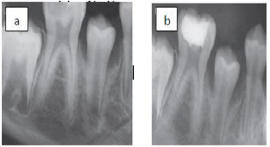

Figure 2: Direct pulp capping in lower premolar.

a) A premolar tooth capped directly with MTA. B) Histologic section after six months shows formation of dentine bridge.

Figure 3: Direct pulp capping in lower molar. a) Preoperative radiograph shows extensive caries.

b) The decay was removed and pulp exposure was capped by MTA.

Figure 4: Partial pulpotomy in upper central incisor.

a) Preoperative radiograph shows traumatic pulp exposure.

b) Partial pulpotomy capped with MTA.

c) Postoperative radiograph shows complete root formation.